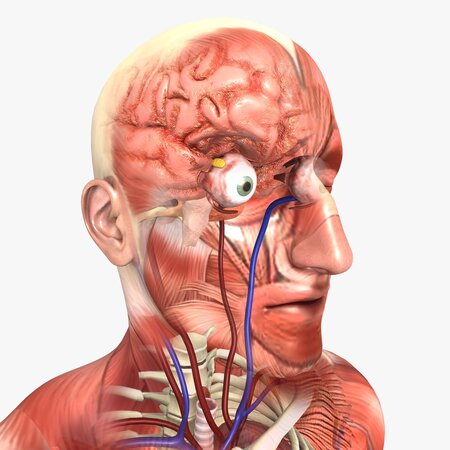

It contains:

Respiratory system | Heart | Diaphragm | Digestive system | Kidneys with bladder | Liver | Stomach